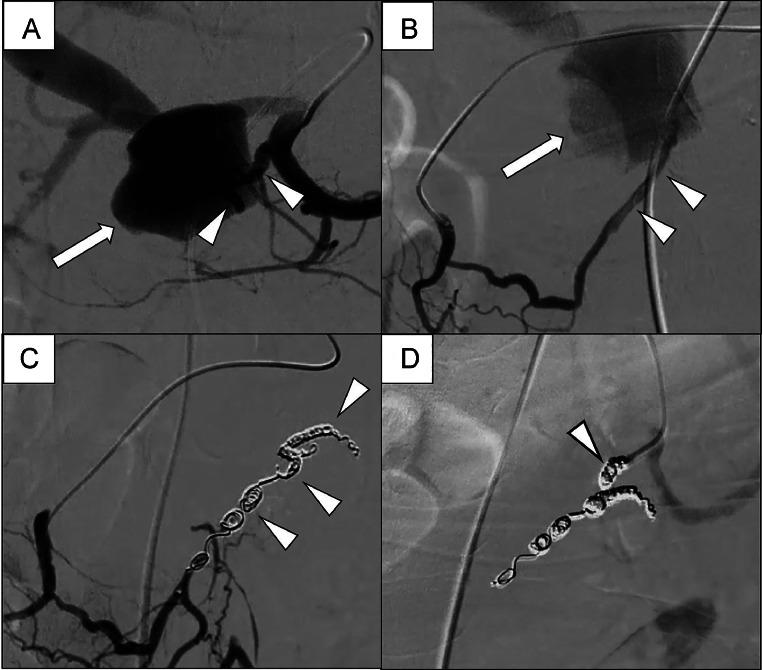

Arterioportal fistula (APF) combined with a visceral artery pseudoaneurysm is an exceptionally rare and critical vascular disorder of the abdominal viscera, with pseudoaneurysm rupture being potentially fatal and severe APF leading to portal hypertension, both of which necessitate immediate intervention. An 87-year-old woman with a history of pancreatitis presented with upper abdomen and back pain. Laboratory tests revealed elevated amylase levels and severe anemia. A computed tomography (CT) scan showed a large dorsal pancreatic artery (DPA) pseudoaneurysm with a fistula to the main portal vein. Given her advanced age, surgery was deemed high-risk, and endovascular treatment was selected. Transcatheter arterial embolization was successfully performed using coils to embolize the DPA pseudoaneurysm. A follow-up CT 1 week postprocedure confirmed the absence of a pseudoaneurysm and no further progression of anemia.

动脉门静脉瘘(APF)合并内脏动脉假性动脉瘤是一种极为罕见且严重的腹部内脏血管疾病,假性动脉瘤破裂可能致命,严重的APF会导致门静脉高压,这两种情况都需要立即干预。一名有胰腺炎病史的87岁女性出现上腹部和背部疼痛。实验室检查显示淀粉酶水平升高和严重贫血。计算机断层扫描(CT)显示胰背动脉(DPA)有一个大的假性动脉瘤,并与门静脉主干形成瘘管。鉴于其高龄,手术被认为风险很高,因此选择了血管内治疗。使用线圈成功进行了经导管动脉栓塞术,以栓塞DPA假性动脉瘤。术后1周的随访CT证实假性动脉瘤消失,贫血未进一步加重。